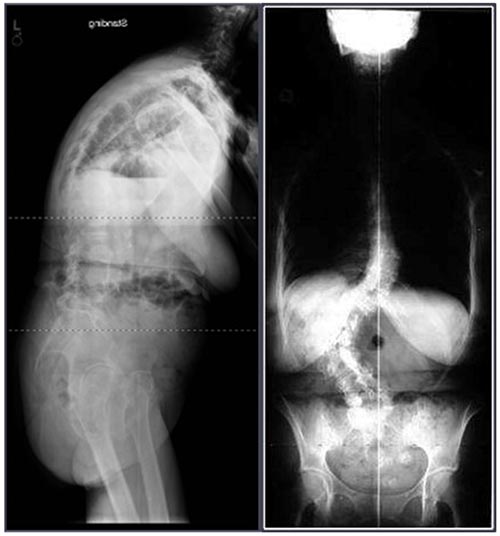

As radiografias panorâmicas são fundamentais na posição frente e perfil, devem incluir a pelve e ambos os quadris. Na radiografia em perfil o joelho deve estar esticado com isso é possível avaliar o alinhamento global e segmentar, além de obter medidas do equilíbrio sagital global, e do equilíbrio espinopélvico, fundamental para o entendimento da deformidade, radiografias em flexão e extensão no perfil também podem ser obtidas para avaliação das instabilidades.

Figura 15. Escoliose do Adulto.